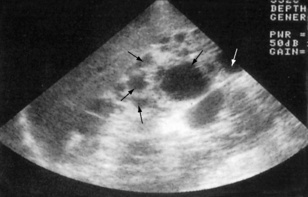

Ultrasonography

Ultrasonography is a non-invasive technique that involves high-frequency sound waves. It can accurately assess the size, shape and position of the kidney, and can also distinguish solid masses and renal cysts (Figs 8.17 and 8.18). Dilatation of the pelvicalyceal system and upper ureters can also be detected – suggesting the presence of urinary tract obstruction. This is a major cause of reversible renal failure, and can be treated if detected early enough. Transrectal ultrasound (TRUS) can also assess prostate size and be used to guide a prostate biopsy (Fig. 8.19). Renal vein thrombosis can be detected with Doppler ultrasonography, and arterial Doppler studies can be used to identify renal artery stenosis. The specificity and sensitivity of ultrasound investigations are very operator-dependent.

image

Fig. 8.17 Ultrasound scan showing the typical appearance of polycystic kidneys. There are multiple cysts (arrows) in the parenchyma.

(From Lloyd-Davis RW et al, 1994. Color atlas of urology, 2nd edn. Mosby Year Book.)